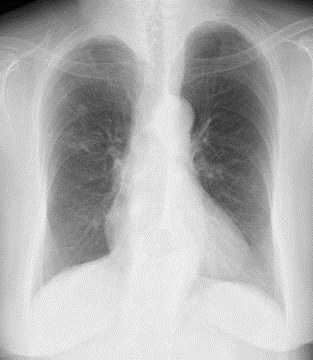

当クリニックでの胸部X線撮影は、前回の画像と今回の画像をコンピューターで解析し、新規の病変を発見しやすくする画像処理を行っています。定期検査での新たな病変の検出に有用です。